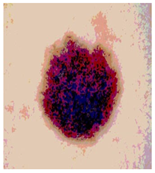

![]() | ![]() | ![]() | ![]() |

| Img1 | --- Pixel Intensity (0–255) ---> | ||

| Img2 | --- Pixel Intensity (0–255) ---> | ||

| Img3 | --- Pixel Intensity (0–255) ---> | ||

| Img4 | --- Pixel Intensity (0–255) ---> | ||

| Img5 | --- Pixel Intensity (0–255) ---> | ||

| Img6 | --- Pixel Intensity (0–255) ---> | ||

| Img7 | --- Pixel Intensity (0–255) ---> | ||

| Img8 | --- Pixel Intensity (0–255) ---> | ||

| Img9 | --- Pixel Intensity (0–255) ---> | ||

| Img10 | --- Pixel Intensity (0–255) ---> | ||